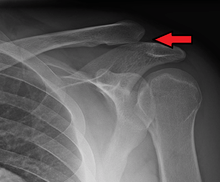

| A Separated Shoulder XRay modified to easily show bones. Notice the separation between the end of the collarbone and the scapula. | |